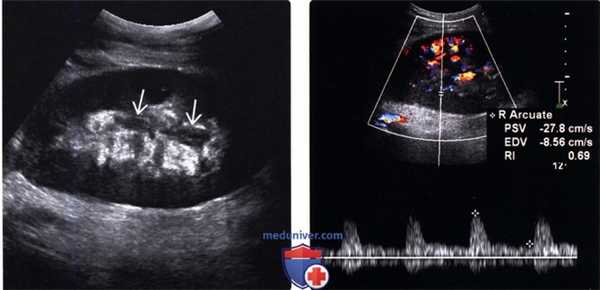

(Левый) Продольный ультразвуковой срез трансплантата почки от живого родственного донора с подтвержденным при биопсии острым клеточным отторжением средней степени тяжести. Изменения в почке, за исключением утолщения уротелия, отсутствуют.

(Правый) На продольном УЗ срезе с импульсно-волновой допплерографией у того же пациента визуализируется нормальный ток в диастолу, а индекс резистентности остается в пределах нормальных значений = 0,69.